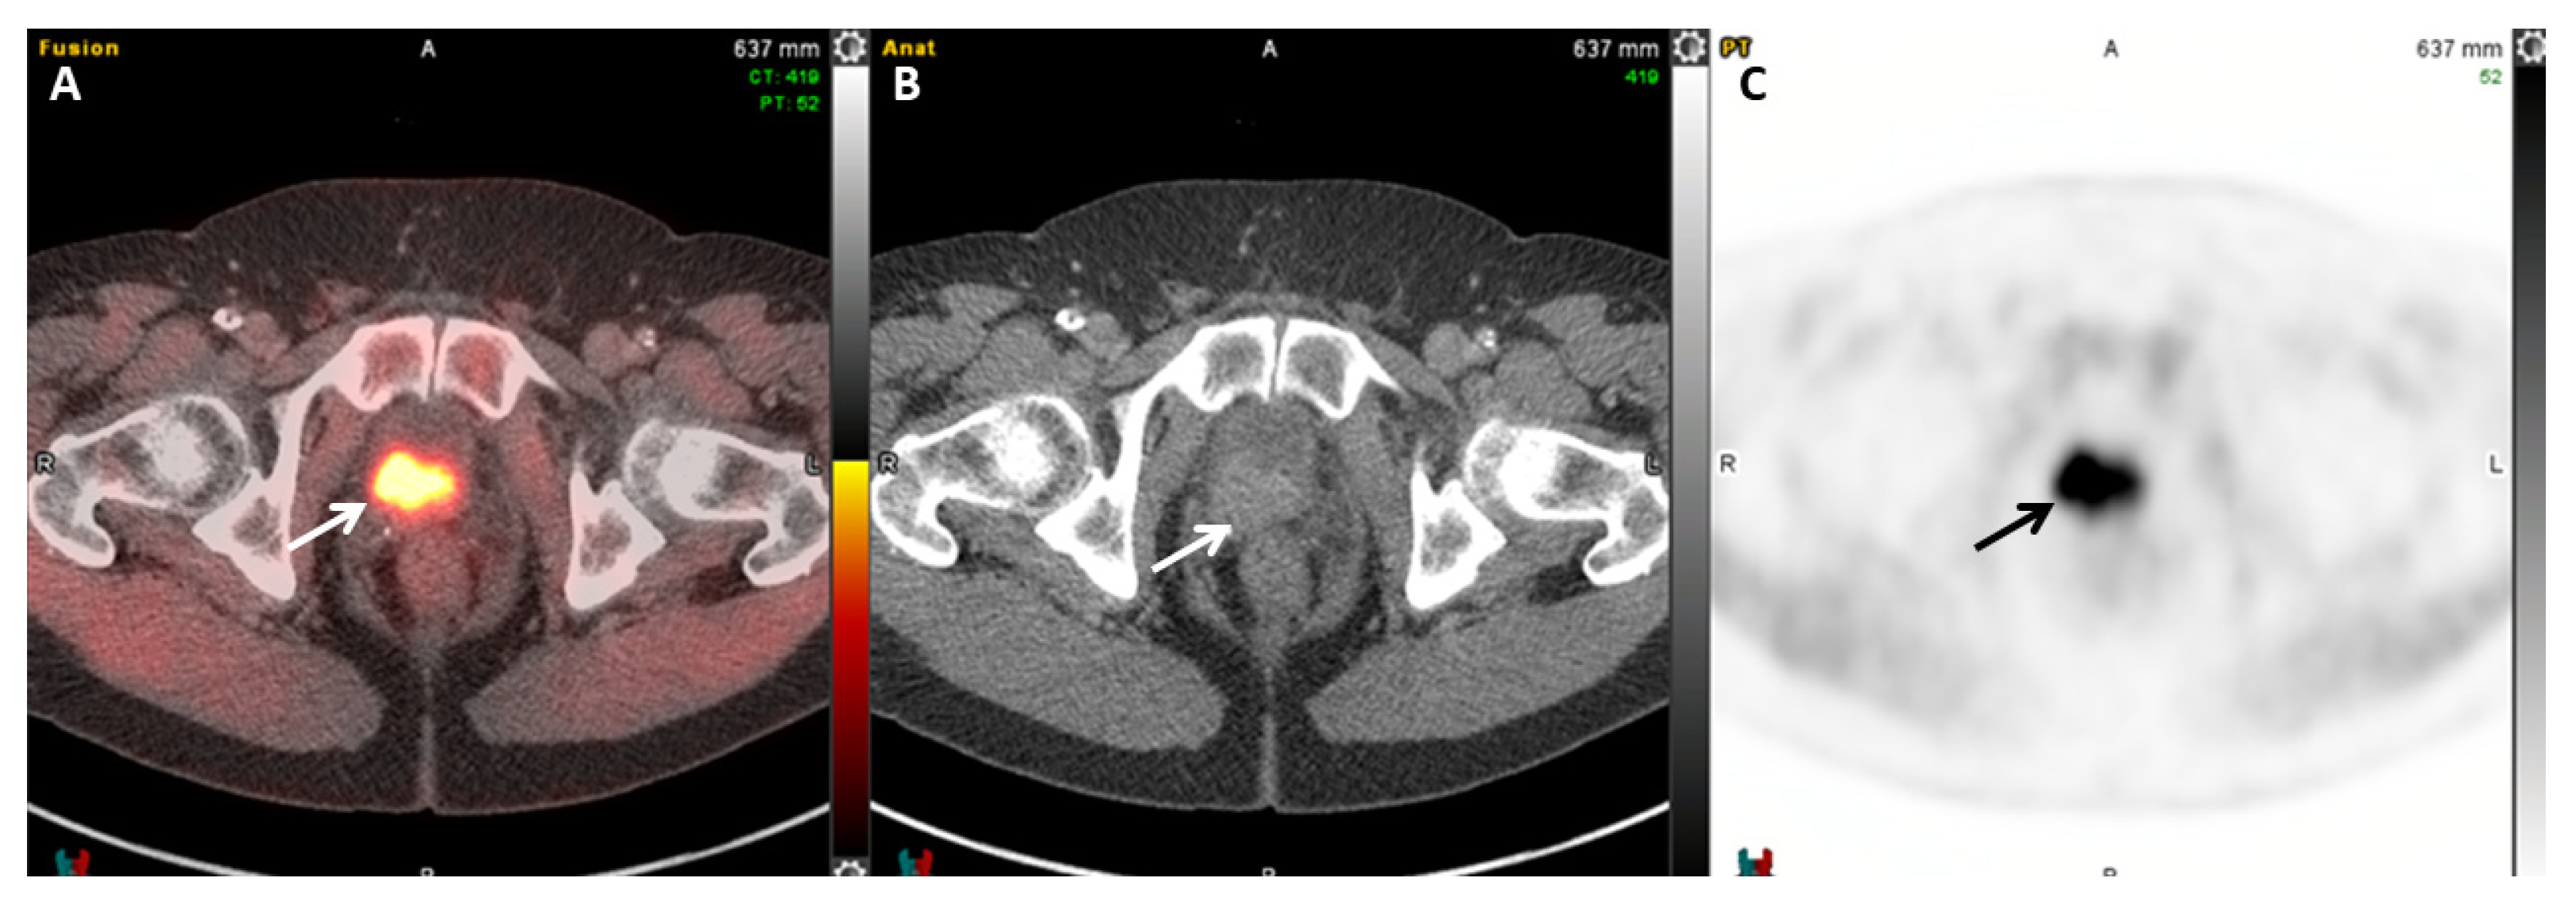

- Calais, J.; Ceci, F.; Eiber, M.; Hope, T.A.; Hofman, M.S.; Rischpler, C.; Bach-Gansmo, T.; Nanni, C.; Savir-Baruch, B.; Elashoff, D.; et al. 18F-fluciclovine PET-CT and 68Ga-PSMA-11 PET-CT in patients with early biochemical recurrence after prostatectomy: A prospective, single-centre, single-arm, comparative imaging trial. Lancet Oncol. 2019, 20, 1286–1294. [Google Scholar] [CrossRef]